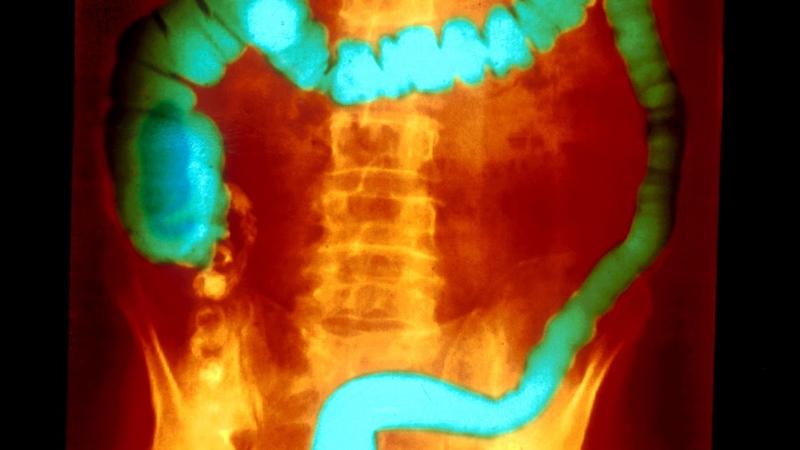

Ulcerative colitis (UC) is an autoimmune disease that causes the immune system to attack the colon, leading to a range of painful signs and symptoms, both in the gastrointestinal (GI) tract and in other parts of the body. The condition causes long-term inflammation of the cells that line the colon, resulting in sores called ulcers. Like most autoimmune diseases, UC has no known cure, but treatment can significantly reduce the signs and symptoms of the disease and possibly even lead to long-term remission.